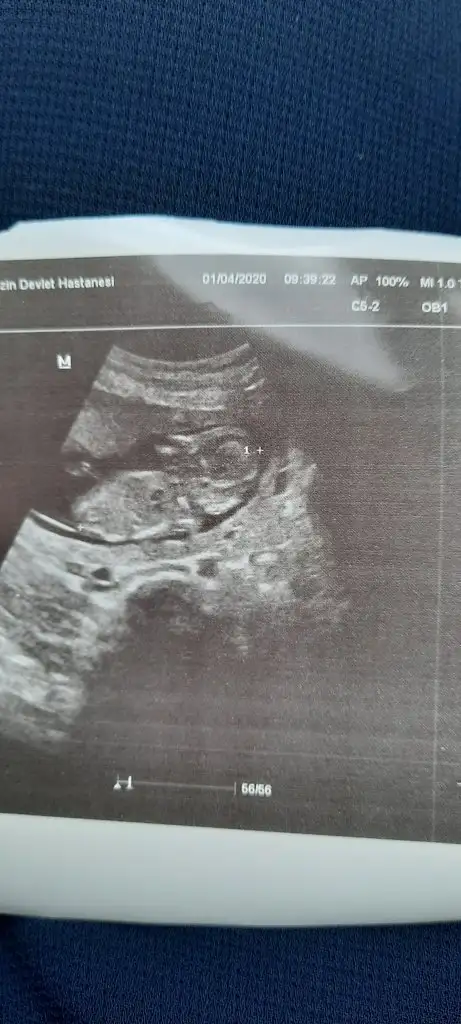

10+5 iz bizede bi tahminde bulunabilirmisiniz çok merak ediyorum cinsiyetini